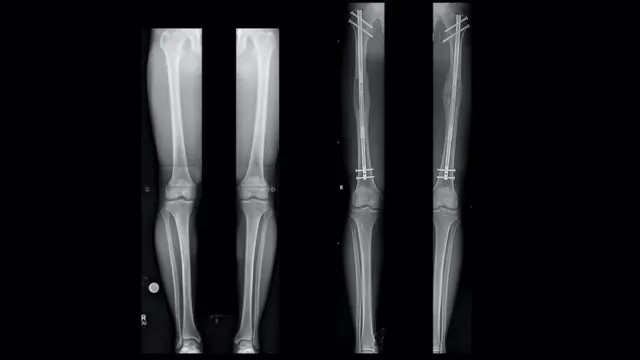

ছবির উৎস, Dr S. Robert Rozbruch

প্রথমে পায়ের হাড়ে একটি ছিদ্র করা হয়।

তার পর সেই হাড় কেটে দু-টুকরো করে তার ভেতরে একটি ধাতব রড ঢুকিয়ে দিয়ে তা স্ক্রু দিয়ে এঁটে দেয়া হয়।

এর পর রডটার দৈর্ঘ্য প্রতিদিন এক মিলিমিটার করে ধীরে ধীরে বাড়ানো হয়।

এভাবে রোগীর ইচ্ছা অনুযায়ী উচ্চতা অর্জন করা, এবং হাড় জোড়া লাগা পর্যন্ত এ প্রক্রিয়া চলে।